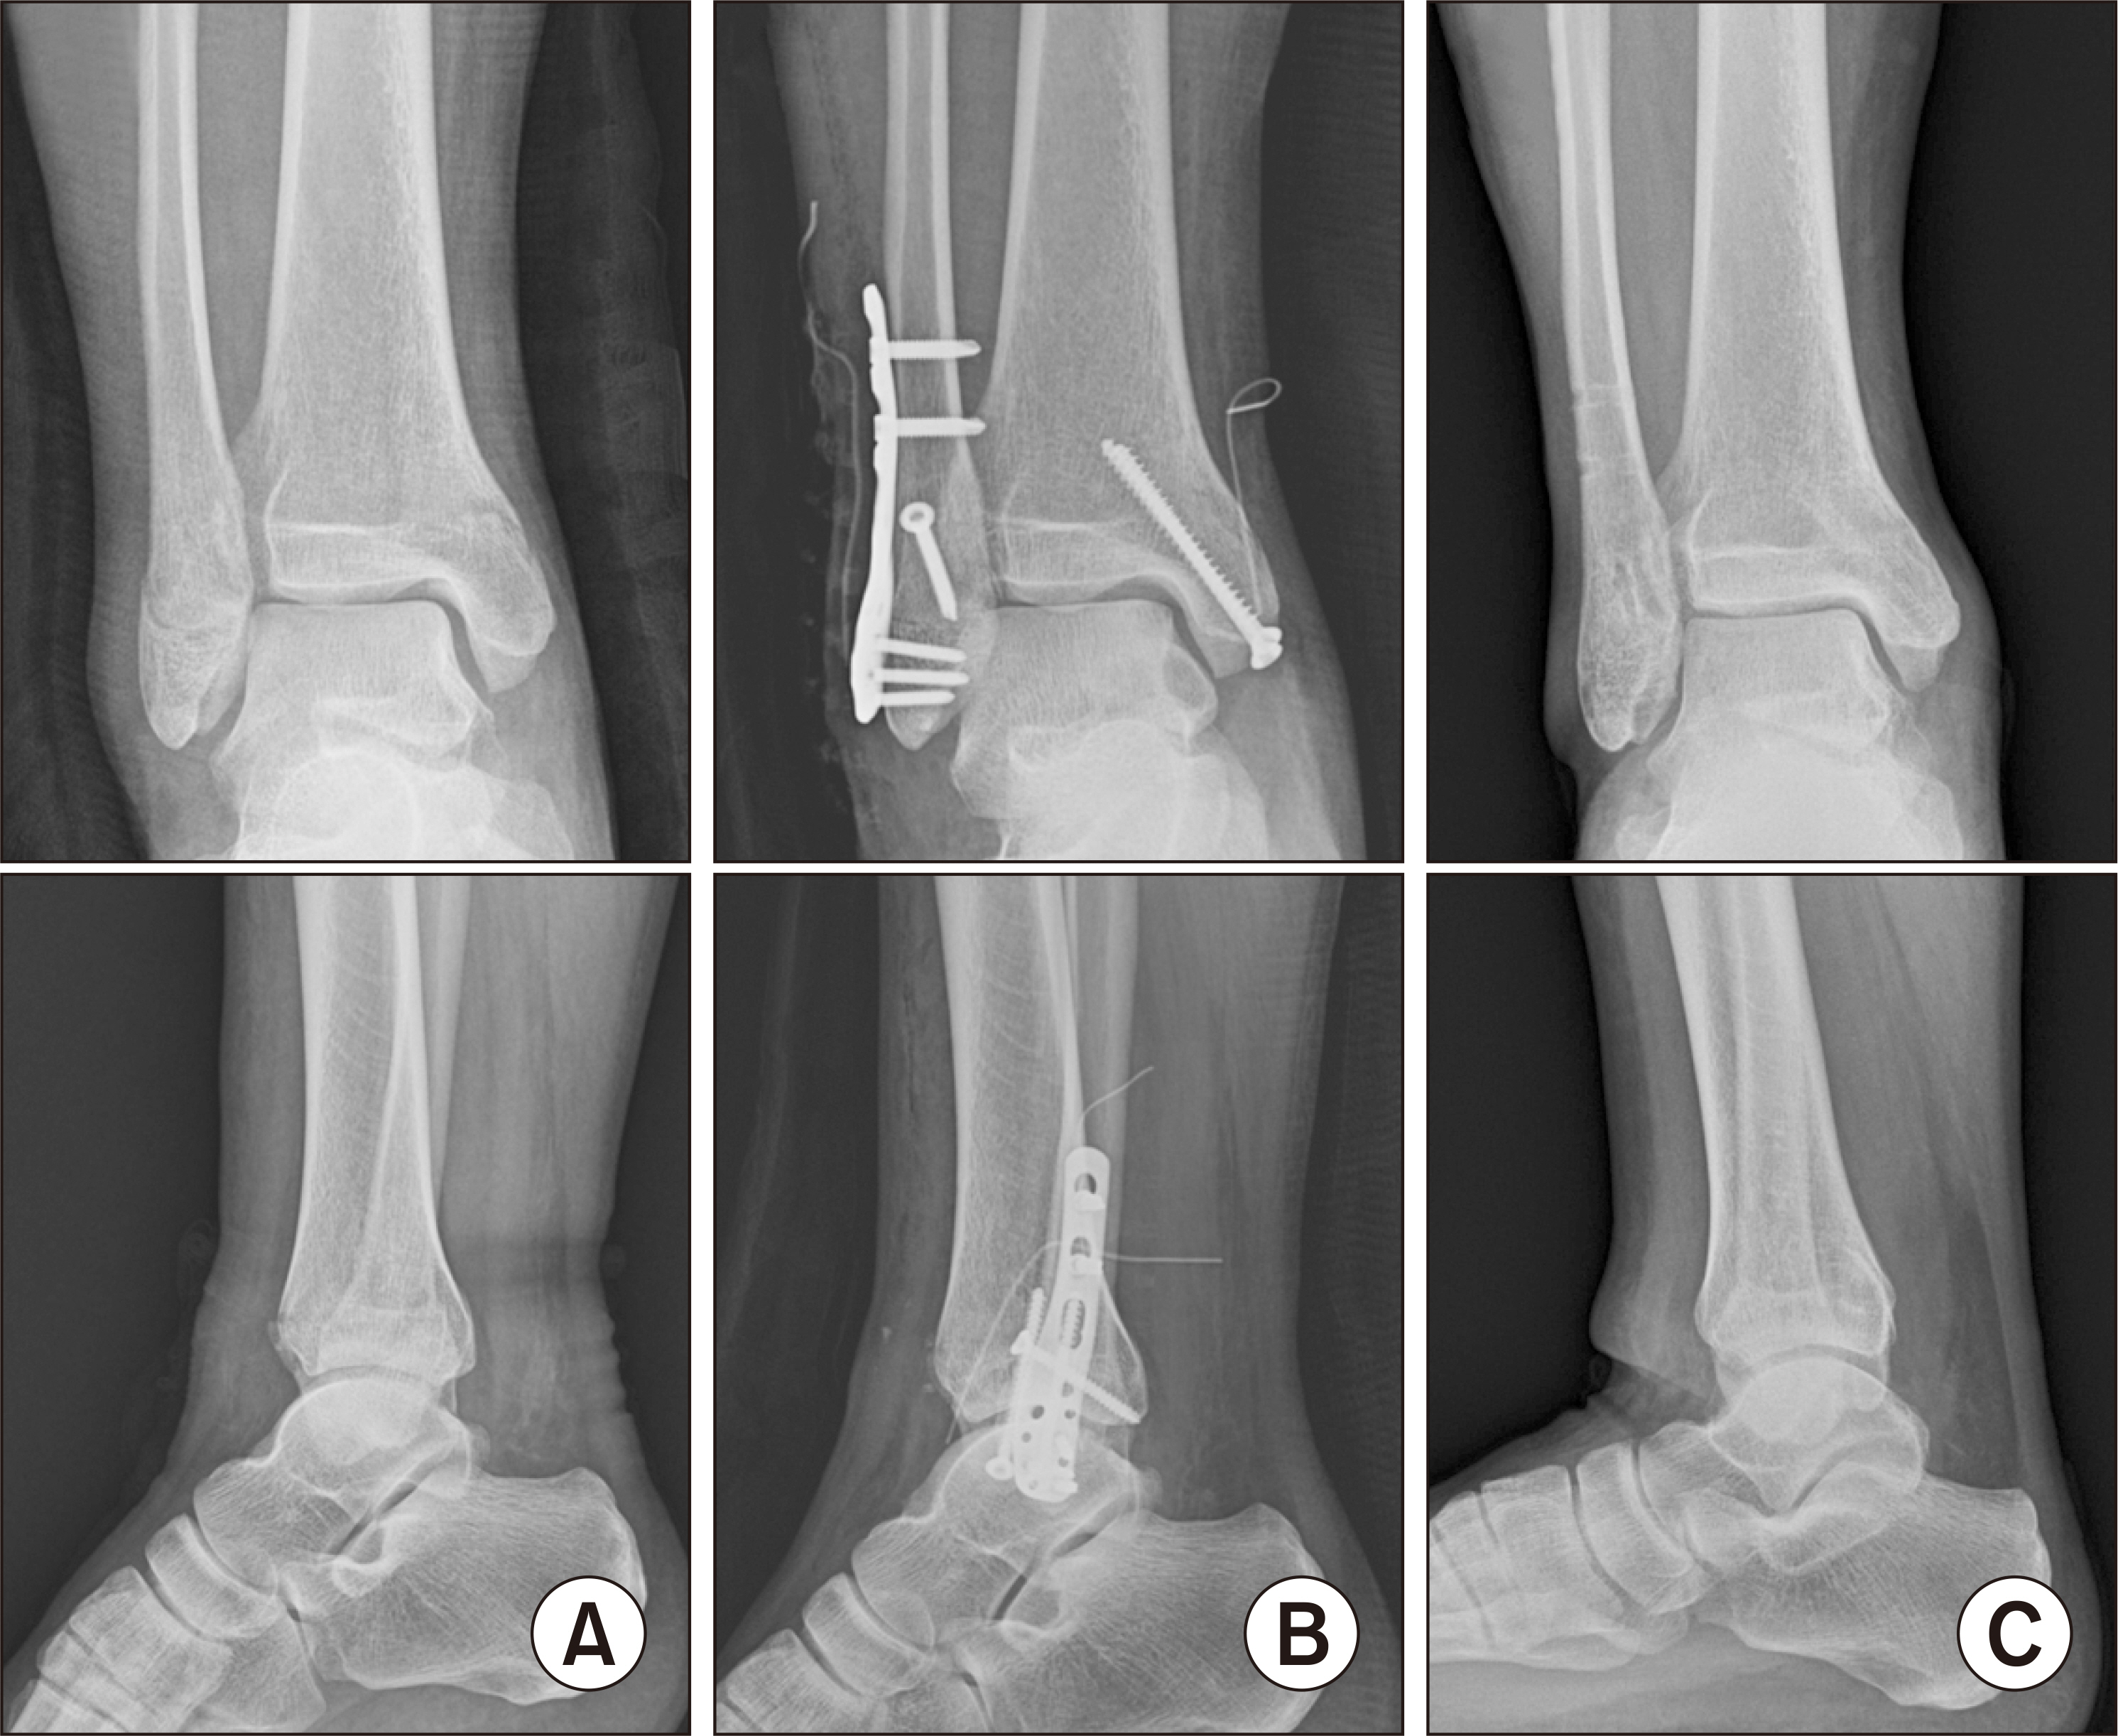

Comparison of Outcomes Using Cortical Lag Screws Versus Cancellous Position Screws for Fibula Fixation in Weber Type B Rotational Ankle Fractures

Ankle fractures are common in the orthopedic field. Lateral malleolar fractures are often treated with lag screws and locking plates. Cortical screws are typically used as lag screws to achieve absolute stability through compression. In osteoporotic bone, however, achieving sufficient compression with cortical screws can be challenging. Cancellous screws may offer better fixation in metaphyseal bone. This study compared the outcomes of using cortical screws as lag screws and cancellous screws as position screws for lateral malleolar fixation.

This retrospective study included patients who underwent surgery for Weber type B ankle fractures at the authors’ hospital between March 2019 and March 2022. The patients were divided into two groups based on the screw type: cortical lag screws (n=70) and cancellous position screws (n=35). In both groups, a locking plate was applied in the same manner after screw fixation. The outcomes were evaluated using the visual analog scale (VAS), Olerud-Molander score (OMS), foot and ankle outcome score (FAOS), and foot function index (FFI). Complications, such as fixation failure, nonunion, and malunion, were recorded.

For the fixation of Weber B fibular fractures, cortical lag screws and cancellous position screws showed comparable clinical outcomes. Cancellous screws with plate fixation may offer a viable alternative in cases with poor bone quality or difficulty applying lag screw techniques.

Figure